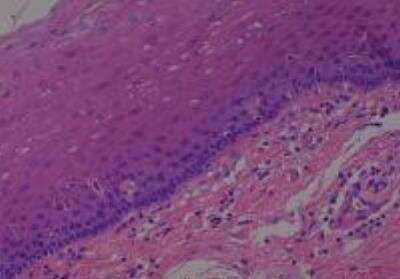

Hematoxylin & Eosin Stain: Human Common Tissue MicroArray (Normal Adjacent) [NBP2-30215] - 102. Stomach